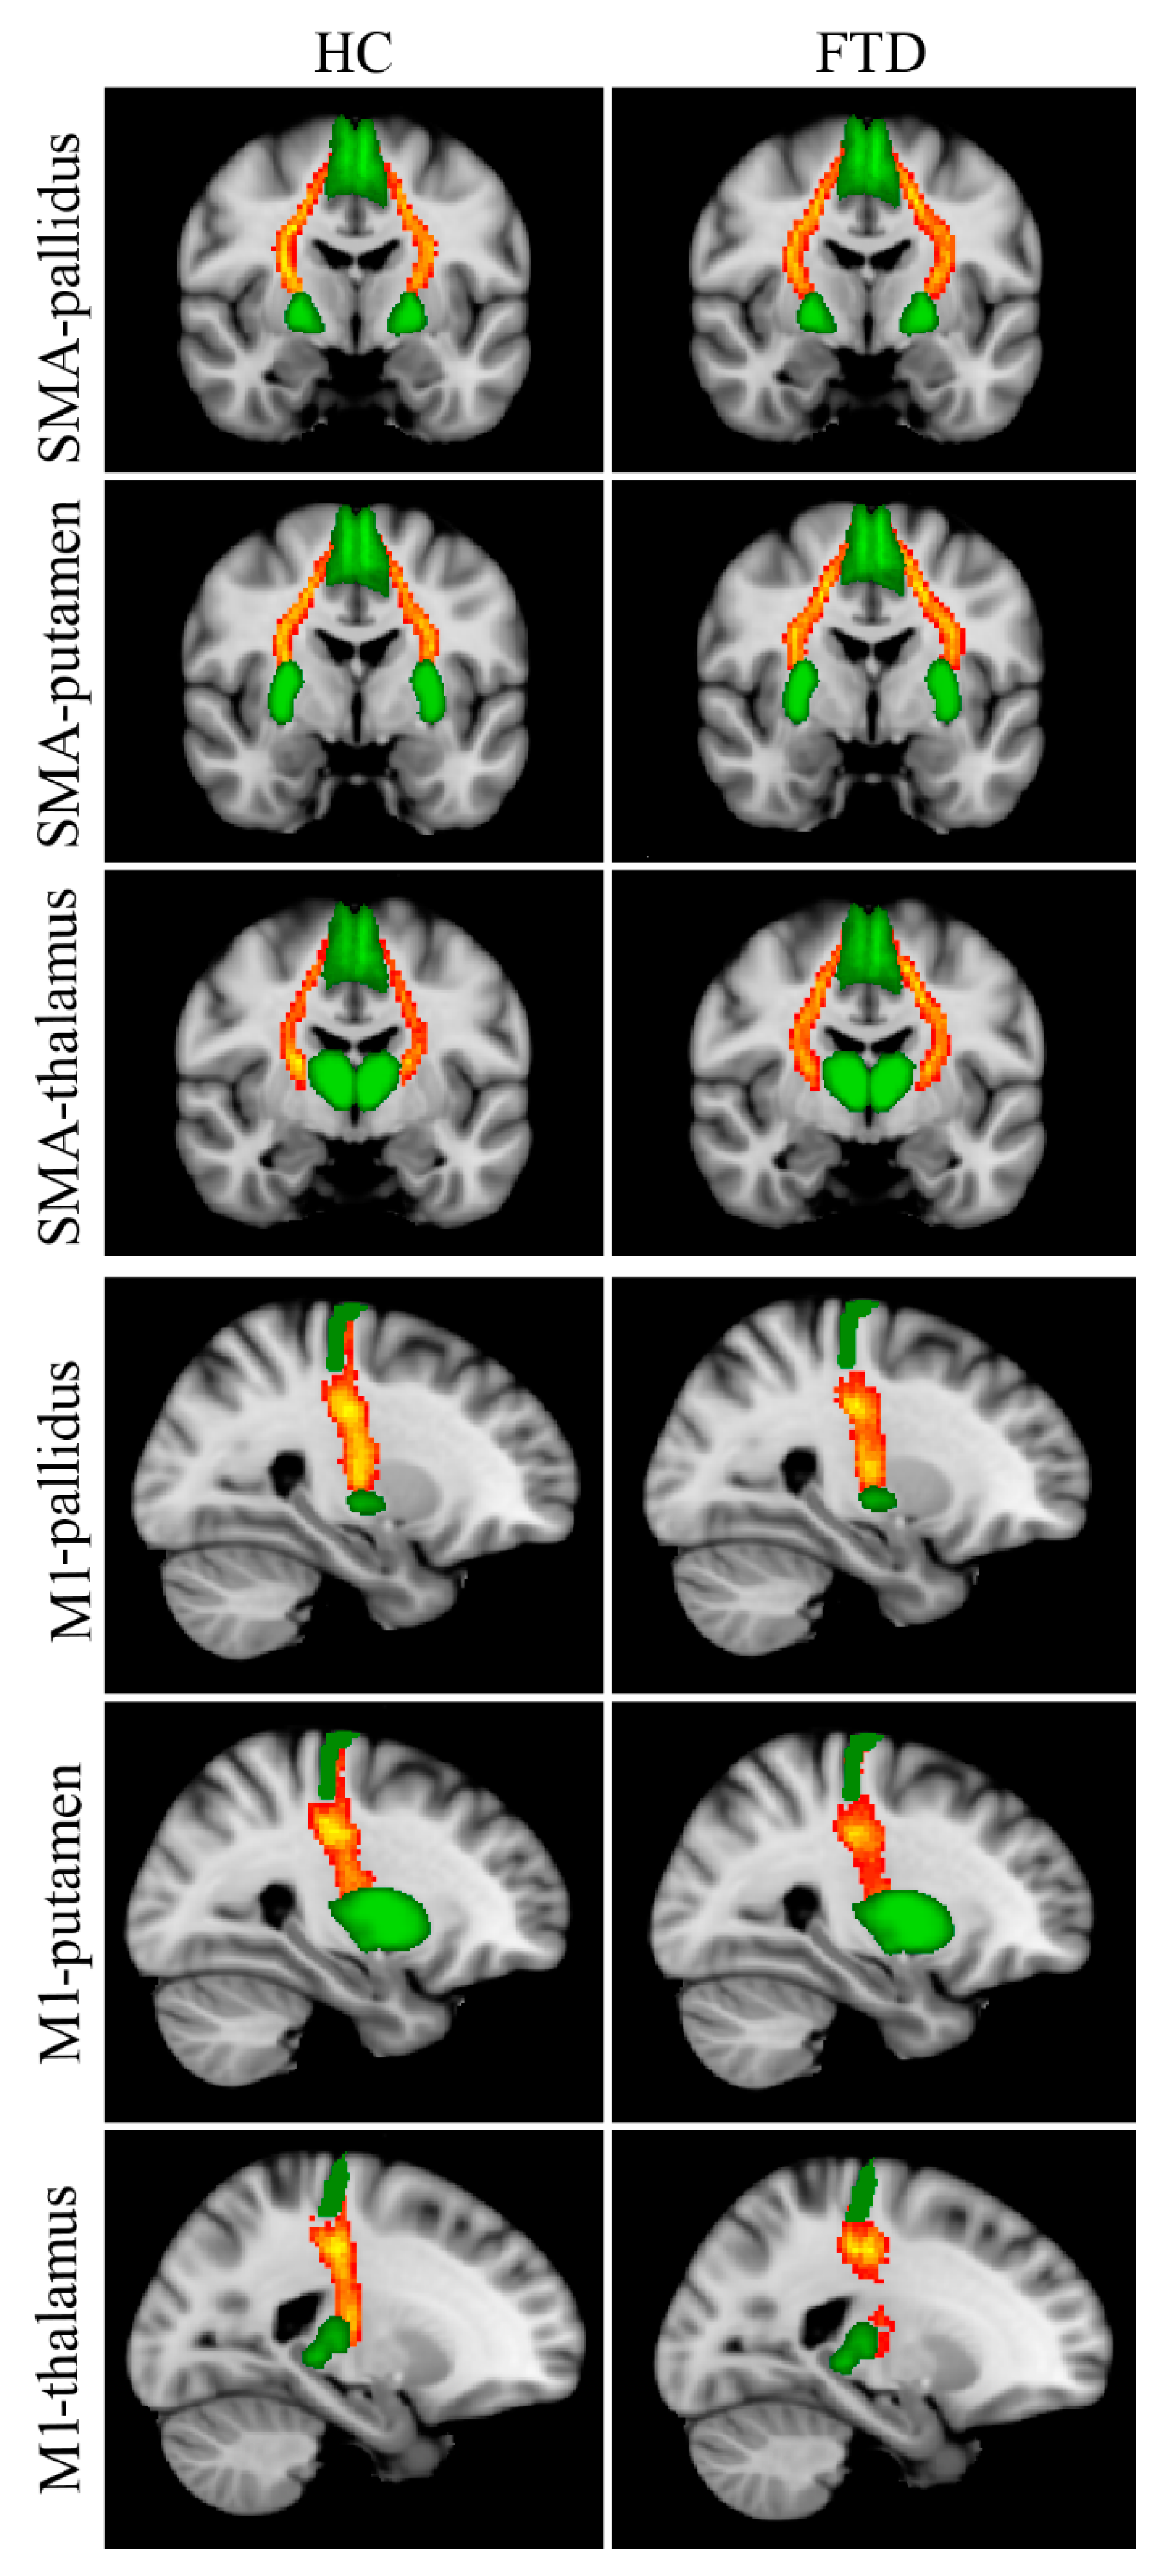

Reconstructed WM tracts, i.e., SMA-pallidus, SMA-putamen, SMA-thalamus, M1-pallidus, M1-putamen, M1-thalamus, are shown in Figure 2. The Kruskal–Wallis test revealed significant between-group FA differences in all tracts connecting the SMA with subcortical nuclei (Table 3); post hoc tests showed significantly lower FA values in Park+ patients with respect to controls for each tract. No significant differences were found between Park− patients and the other two groups. Between-group differences in FA for M1-pallidus, M1-putamen, and M1-thalamus did not survive Bonferroni correction.

Figure 2.

Reconstructed white matter pathways in healthy controls (HC) (left panel) and all FTD patients (Park+ and Park−, right panel) overlaid onto the MNI152 standard brain. Red-yellow colors reflect the extent of spatial overlap of reconstructed tracts between participants, with red indicating at least 40% overlap and yellow indicating 100%. Green areas represent regions of interest used for probabilistic tractography. Differences in fractional anisotropy (FA) values between controls and FTD patients with and without parkinsonism are reported in Table 3.